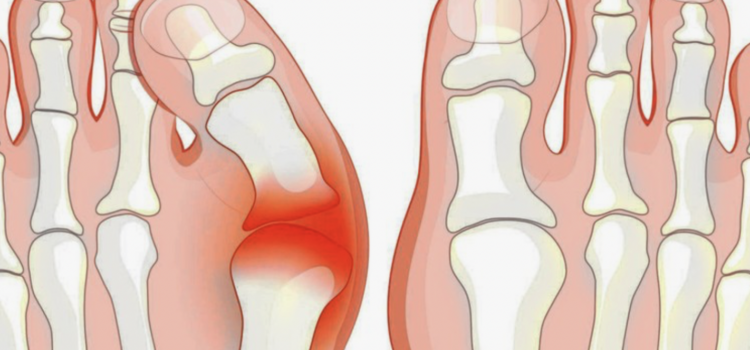

Bagi banyak orang, berdiri atau berjalan adalah aktivitas otomatis yang tidak memerlukan pemikiran ekstra. Namun, bagi mereka yang hidup dengan kondisi valgus—deformitas pada sendi pangkal jempol kaki—setiap langkah melibatkan perjuangan mekanis yang nyata. Masalah utama yang sering muncul bukanlah sekadar bentuk

Keseimbangan Langkah: Pentingnya Distribusi Beban untuk Mencegah Kelelahan Akibat Valgus